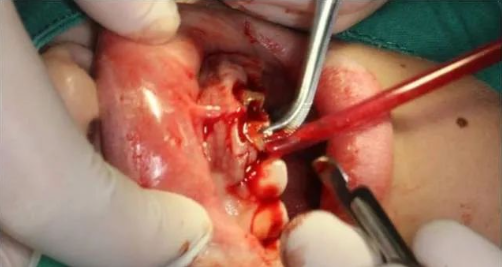

局麻下翻瓣

术中

翻瓣后清除炎性组织

颈缘骨修整